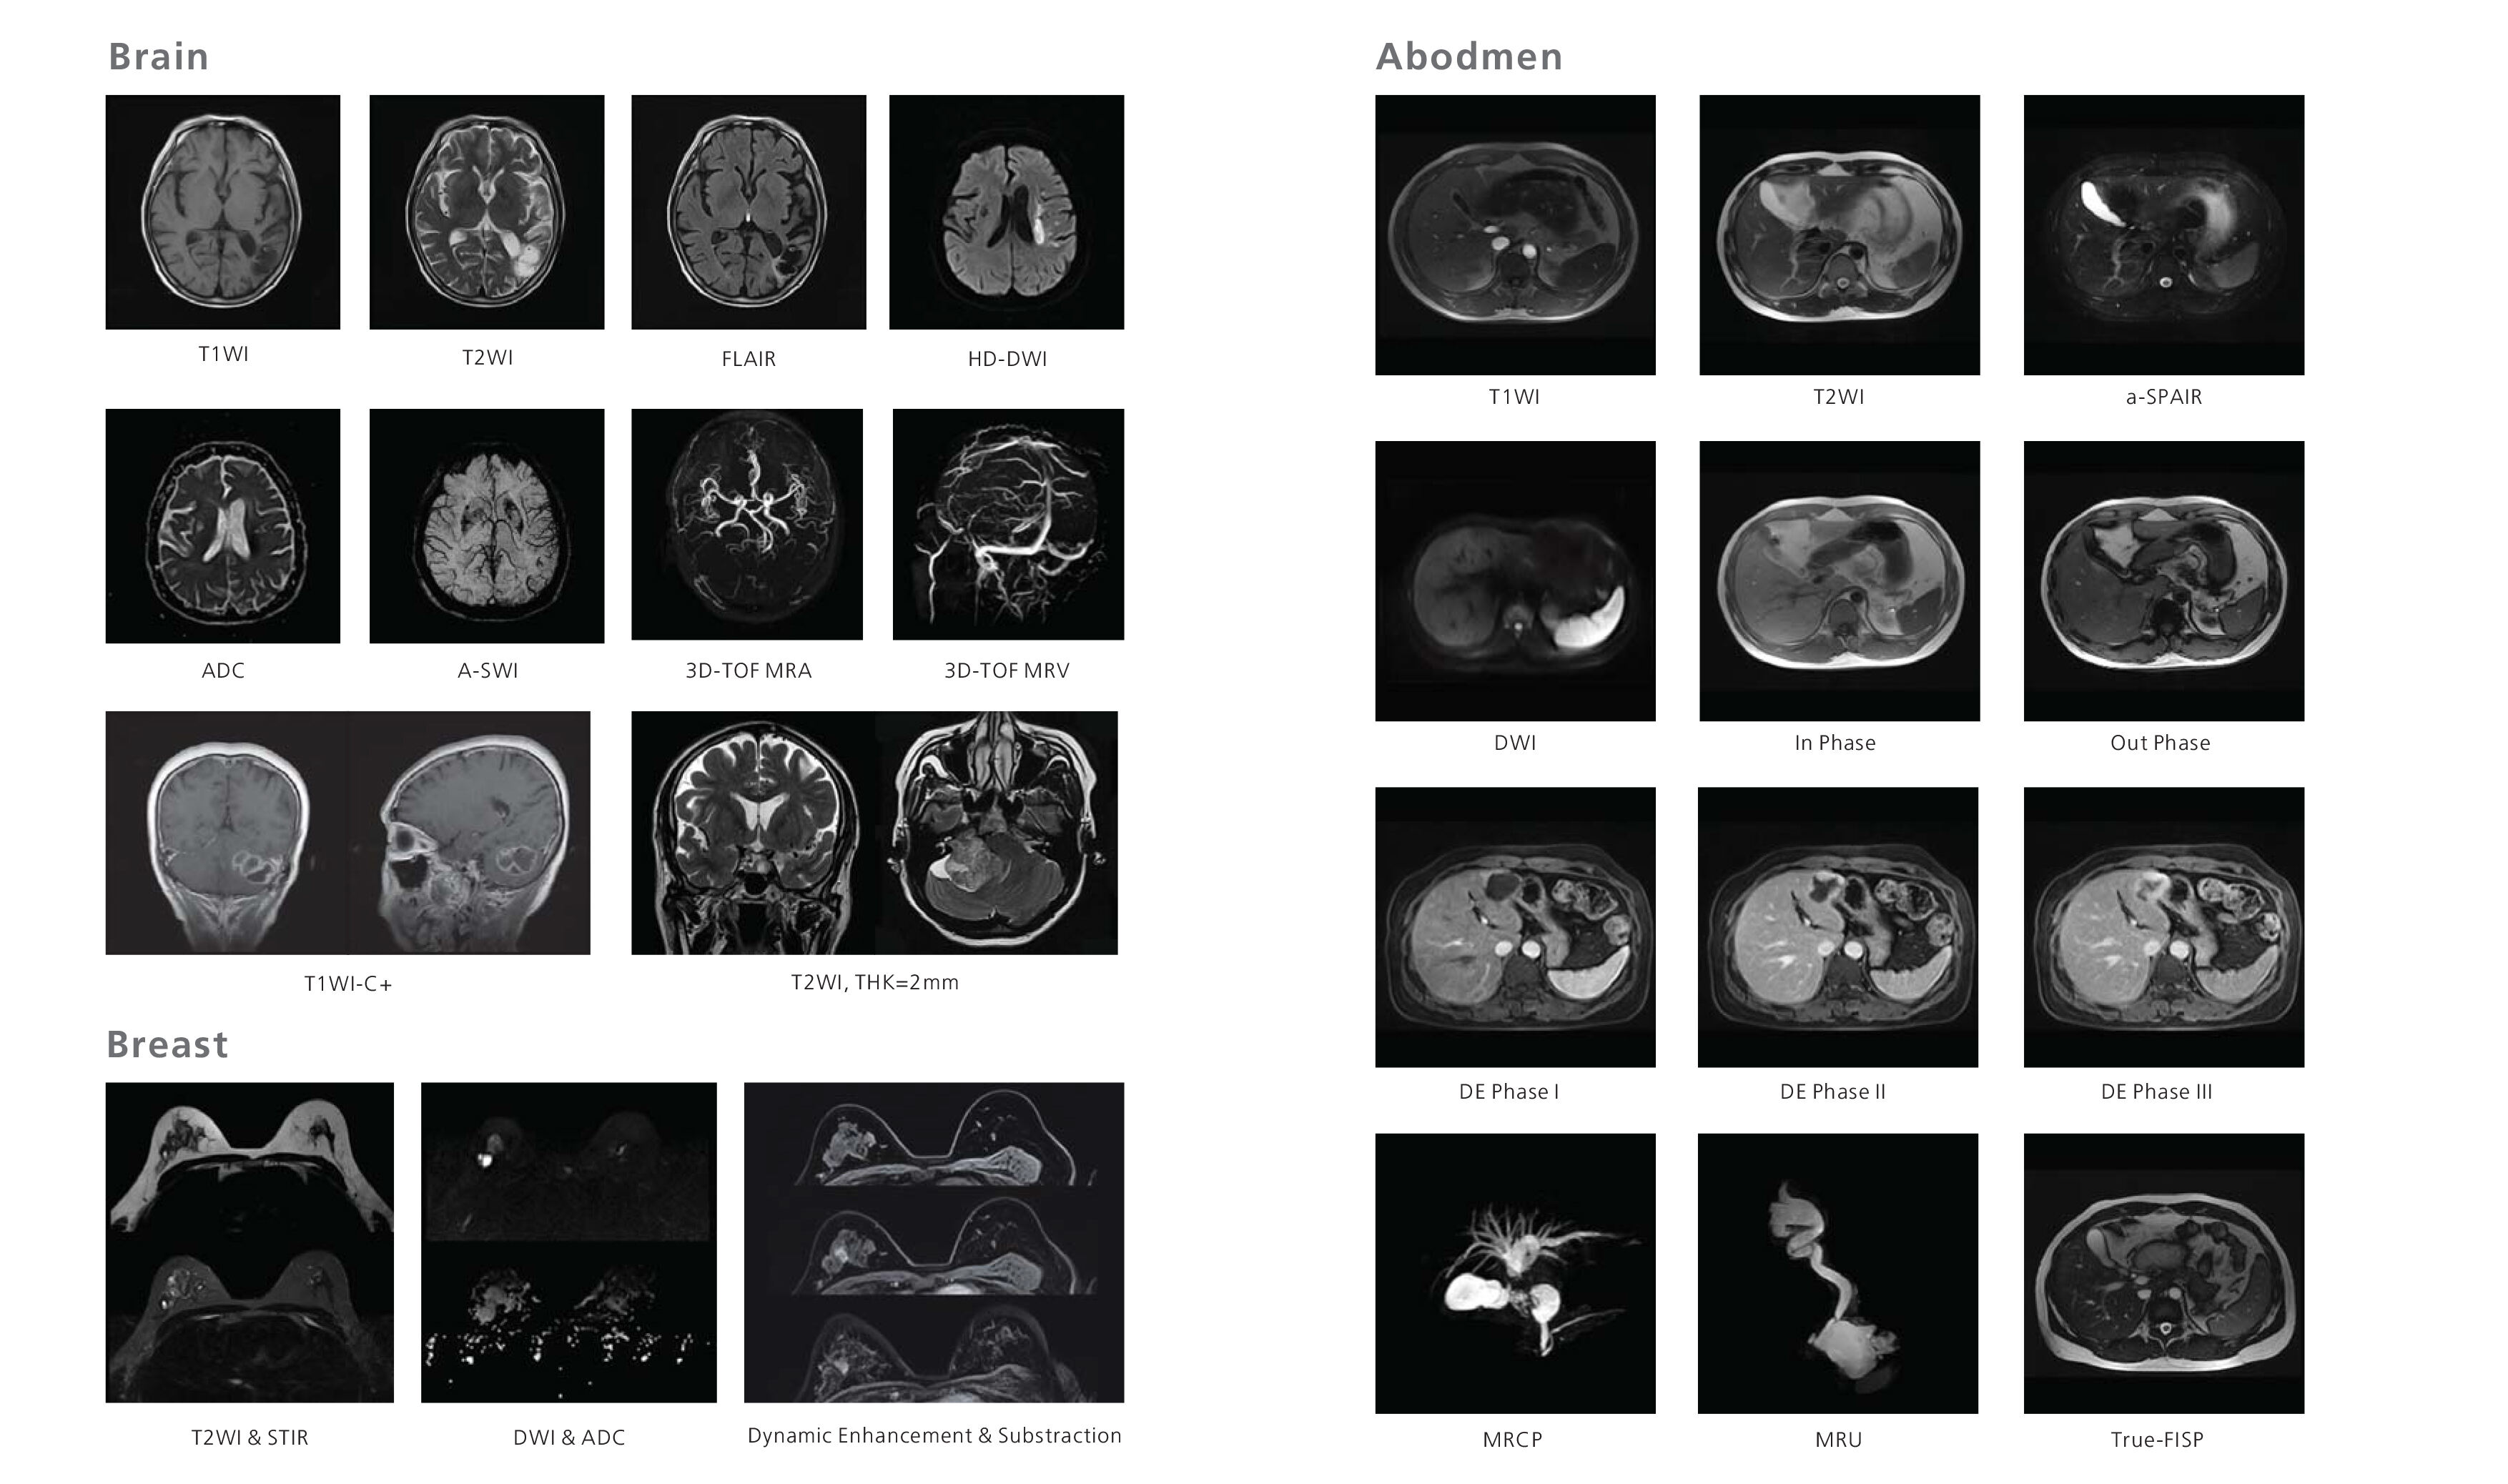

SuperMark 1.5T is a latest generation superconducting MRl system based on over 30 years of experience in research and development, which focuses on user's concerns. This system is equipped with a new upgraded hardware and software platforms with A-combi and Al technologies that benefit users a lot and deliver patients with more comfortable experiences. It features new user-friendly design, faster imaging speed, higher image quality and greatly improved work efficiency.

SuperMark 1.5T provides not only conventional pulse sequences and basic clinical applications, but also advanced functional applications. Moreover, it adopts brand new professional APEX operation system which ensures easy operation and fast diagnosis